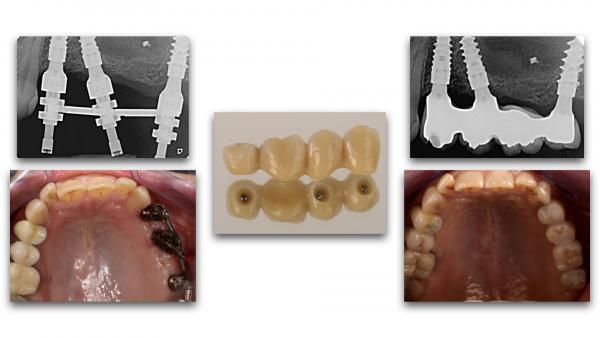

La démocratisation de nouvelles techniques comme le « Digital Smile Design », l’imagerie 3D, les outils de planification implantaire, les guides chirurgicaux stéréolithographiques, les empreintes optiques, la numérisation des modèles et la production par CFAO de piliers et de restaurations anatomiques optimisant nos profils d’émergence, contribuent à assurer la pérennité des restaurations implantaires à long terme.

De même l’amélioration de la prévisibilité des traitements, la mise en place des protocoles et la simplification des procédures cliniques et de laboratoire permettent aujourd’hui l’optimisation du résultat esthétique des restaurations implantaires, plus que jamais fidèles à la notion de « Biomimétisme ».

Le but de cette communication est de présenter une démarche thérapeutique reproductible, de la planification à la conception des restaurations implantaires unitaires et de grandes étendues, qui permet d’anticiper le résultat de nos traitements devenus de plus en plus complexes et de répondre aux principaux objectifs de l’implantologie moderne.